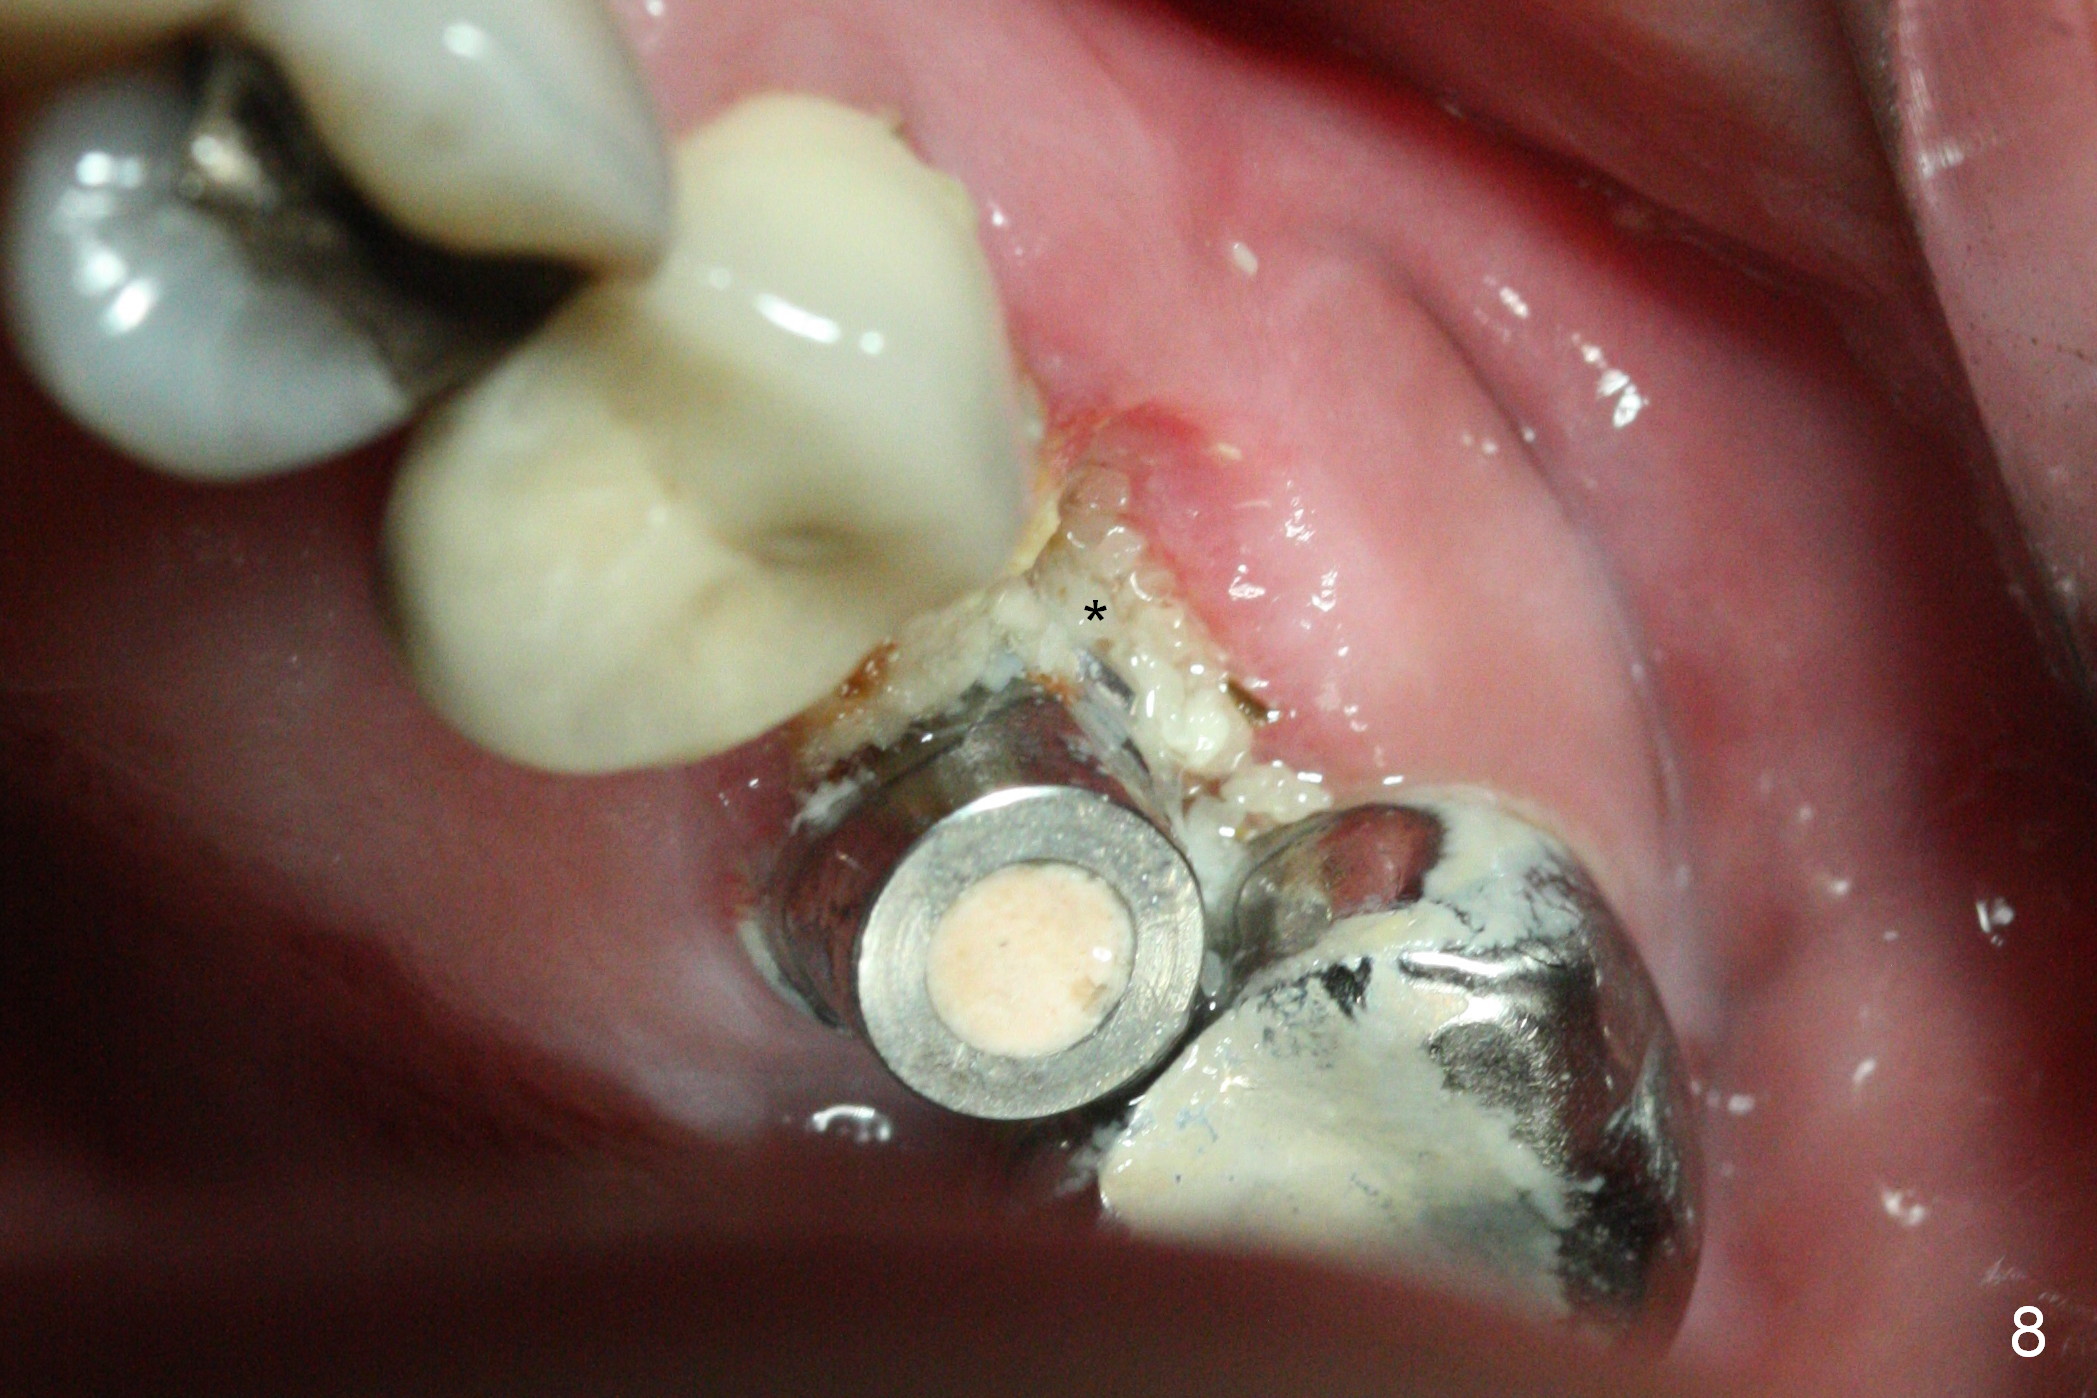

The patient is doing well 9 days postop. The immediate provisional is loose and over-sized. It is removed for trimming and reline; the socket and bone graft (Fig.8 *) are healing. It appears that an angled abutment is required next time of provisional revision. When an angled abutment is being placed 23 days postop (Fig.9), it appears to wiggle the implant due to its long leverage. Instead a healing abutment is placed. The implant is unstable 4.5 months postop with seemingly excessive bone-implant gap (Fig.10 <). The 5.5x9 mm implant is removed. A 5x17 mm tap is used to change the trajectory and sinus lift, followed by 6x17 one (Fig.11). Finally a 6x14 mm tissue-level implant is placed with insertion torque > 50 Ncm (Fig.12; vs. <20 Ncm (Fig.7,10)) and improved trajectory. An immediate provisional is fabricated to prevent the mesial drifting of the tooth #15 (Fig.13 P (*: occlusal clearance)). By using the taps and placing the longer implant, the sinus lift is more obvious (compare Fig.10 and 12 (*)). Sinus lift remains evident 3.5 months postop (Fig.14) with apparently osteointegration (Fig.15).